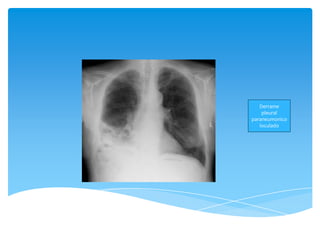

Derrame

pleural

paraneumonico

loculado